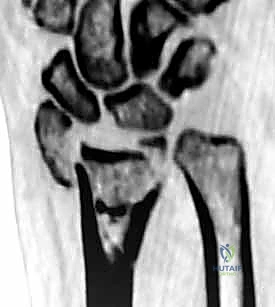

يعتمد الدكتور محمد هطيف على أحدث التقنيات التشخيصية، حيث يبدأ بـ الأشعة السينية (X-rays) في وضعيات متعددة. وفي حالات الكسور المعقدة التي تمتد إلى داخل المفصل، يتم إجراء تصوير مقطعي محوسب (CT Scan) لبناء صورة ثلاثية الأبعاد للكسر، مما يساعد في التخطيط الجراحي الدقيق.

- امتداد الكسر: هل هو خارج المفصل (Extra-articular) أم داخل المفصل (Intra-articular)؟

- درجة التفتت: هل العظم مكسور إلى قطعتين أم مفتت إلى عدة شظايا؟

3. إرجاع الكسر (Fracture Reduction)

تُعد هذه الخطوة الأهم. باستخدام أدوات دقيقة وجهاز الأشعة السينية المباشر في غرفة العمليات (C-arm fluoroscopy)، يقوم الدكتور هطيف بإعادة ترتيب شظايا العظام إلى مكانها التشريحي الأصلي، مع التركيز الشديد على استواء السطح المفصلي.